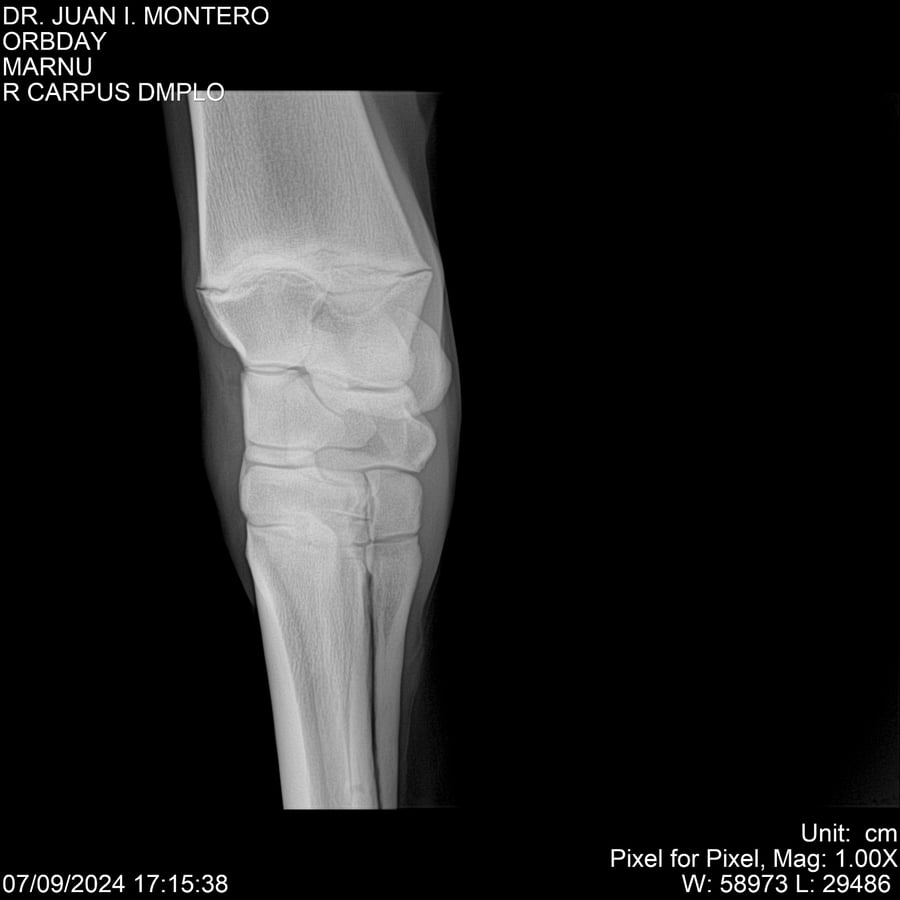

• Empresa: Abelenda N. R., Walter Hugo